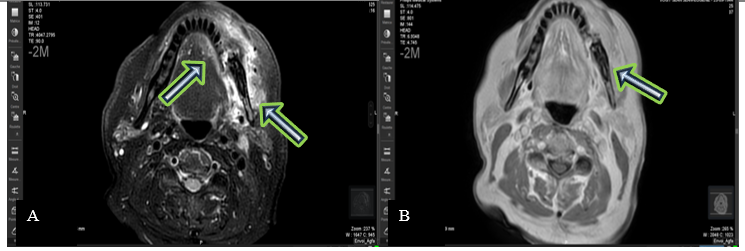

The patient was then referred to an Ear-Nose-Throat (ENT) Doctor who completed the assessment with an Magnetic Resonance Imaging (MRI) of the facial bones. The imaging revealed a fracture of the horizontal branch of the left mandible, with significant surrounding soft tissue infiltration and moderate enhancement, findings that could be compatible with osteomyelitis. No true mass effect or cervical lymphadenopathy was noted.

Figure 3 : Axial MRI images: T2-weighted (A) and T1-weighted (B) sequences showing a left mandibular lesion with high signal intensity, suggestive of a solitary plasmacytoma.

Malignant plasma cells produce cytokines and release an osteoclast-activating factor that stimulates osteoclasts to resorb bone; consequently, on radiographic examination, they appear as well-defined osteolytic lesions with either unilocular or multilocular radiolucency (10,14). According to Lae et al., three radiographic patterns have been described in SBP: multilocular 'soap bubble' lesions, unilocular radiolucency (as seen in our patient) with a cystic appearance, and poorly defined destructive bone resorption (15). CT helps to refine the radiological image and assess the extension toward cortical and soft tissues. MRI remains a valuable imaging modality for detecting bone-involved plasmacytomas, assessing soft tissue involvement and bone marrow infiltration, and evaluating disease throughout the body. Solitary plasmacytomas show low signal intensity on T1-weighted images and high signal intensity on T2-weighted images, with homogeneous enhancement after gadolinium contrast injection (16).